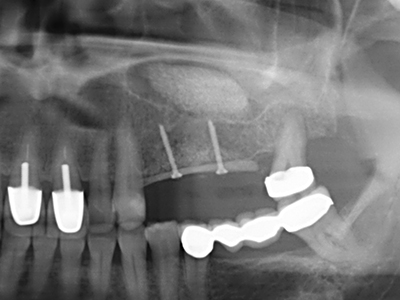

Si es preciso realizar intervenciones quirúrgicas en las que el hueso está en contacto directo con estructuras sensibles, como son los vasos sanguíneos o los nervios, los instrumentos rotativos presentan un enorme potencial de provocar lesiones iatrogénicas. Así, precisamente en la representación de nervios después de una lesión iatrogénica, o en el transcurso de la lateralización de un nervio para resecciones, reconstrucciones o incorporación de implantes, los equipos piezoeléctricos pueden resultar muy útiles para preparar la tapa ósea y retirar las partes de tejido duro cercanas al nervio (fig. 17-20). Por lo general, un ligero contacto del cordón nervioso con el inserto piezoeléctrico no tiene consecuencia alguna; ahora bien, un procedimiento poco cuidadoso con movimientos tipo sierra o piezas de trabajo sobre la base ósea aún existente puede provocar lesiones nerviosas temporales o incluso permanentes. Con todo, el riesgo de sufrir una lesión de este tipo se considera significativamente inferior que en los casos en los que se utilizan sierras y fresas (Pereira, Gealh et al. 2014).

Como ya se ha demostrado en el pasado, básicamente cualquier procedimiento de cirugía de hueso representa una posible indicación para la cirugía piezoeléctrica. Así, la preparación del segmento móvil en la osteogénesis de distracción (fig. 23-25) y en la osteotomía de sándwich puede realizarse con piezas especiales, sin poner en peligro el suministro sanguíneo de la parte crestal, que resulta esencial para el éxito de ambas técnicas (González-García, Diniz-Freitas et al. 2008).